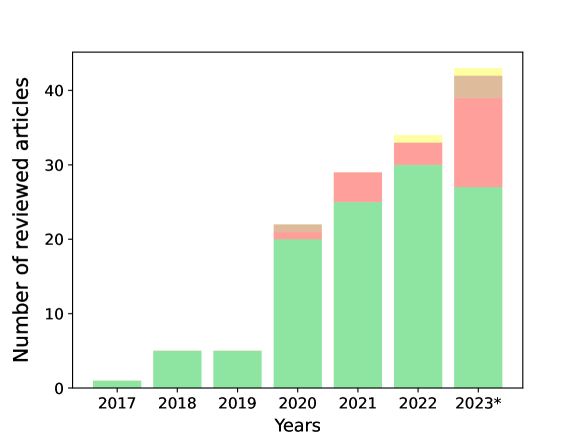

The database search retrieved 2,851 results. After title and abstract screening, the full texts of 206 reported studies were analyzed, but only 140 were found eligible for inclusion. Twenty studies using imaging acquisition other than CT (magnetic resonance imaging (MRI), positron emission tomography (PET), and ultrasound) were excluded. The list of excluded articles and the reasons for exclusion are reported in Section 2.5. Ten additional studies were retrieved after a manual check of the references. A total of 130 studies were included for full-text analysis (Fig. 2). By considering the involved countries (Fig. 3, left panel), China led the ranking with a share of 54.4%, followed by the United States (17.1%), the United Kingdom (5.3%), Canada (3.5%), and Japan (3.5%). In the majority of studies, 3D neural networks (Fig. 3, central panel) were used (51.4%), followed by 2D models (42.7%), and 2.5D (5.8%). By considering the learning type, the vast majority concern studies on supervised learning (83.8%), followed by semi-supervised learning (9.5%), and unsupervised learning (4.4%). Other types of learning (reinforcement, weakly, and continual) are reported in 2.2% of the studies (Fig. 3, right panel). Overall, there is a positive trend in the number of published articles in peer-reviewed journals, included in the present review, even though the data for the year 2023 are available until October 31st (Fig. 4). Notably, there has been a surge in the number of studies on DL for the segmentation of pancreas tumors in 2023. The 130 reviewed studies were published in high-quality peer-reviewed journals with a mean 2023 impact factor of 5.39 (latest available data according to the Web of Science). As can be seen from Fig. 5 the studies were most frequently published in prominent journals in the medical imaging domain, like Medical Imaging Analysis and IEEE Transactions on Medical Imaging, with 11 and 12 publications, respectively. Of note, there are other studies published in leading journals like IEEE Transactions on Pattern Analysis and Machine Intelligence, IEEE Transactions on Image Processing, and Nature Methods.